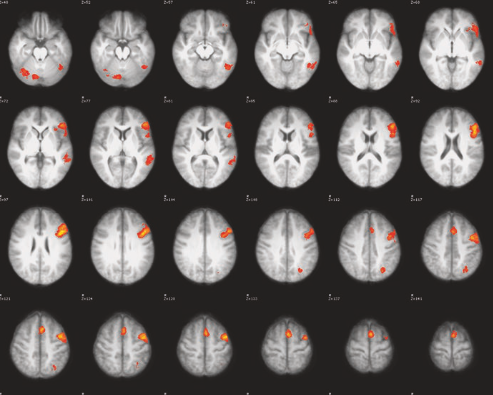

Dr. Benjamin has an extensive background in using language fMRI to map the brain’s language regions to help plan epilepsy surgery. He oversees the clinical language fMRI service at VGH and consults privately to programs on setting up or refining their clinical fMRI service. Dr. Benjamin remains an adjunct Associate Professor at Yale University, where he worked until joining VGH in 2024.